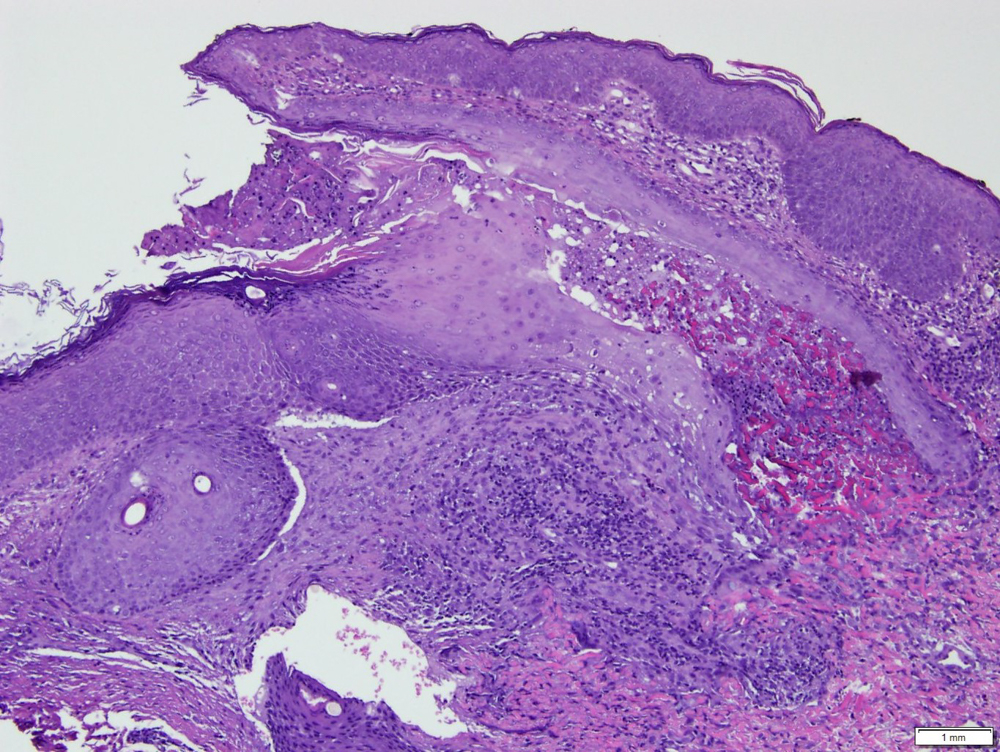

D-penicillamine induced degenerative dermatosis include, among others, elastosis perforans serpiginosa, and pseudo- -pseudoxanthoma elasticum. Elastosis perforans serpiginosa is a rare perforating disease characterized by transepidermal elimination of abnormal elastic fibers. This condition can be idiopathic, reactive or induced by D-penicillamine, commonly used for the treatment of Wilson disease, cystinuria, rheumatoid arthritis or systemic sclerosis. Cutaneous manifestations resembling pseudoxanthoma elasticum but lacking familiar history and ABCC6 mutations have been identified as a D-penicillamine induced dermopathy and called pseudo-pseudoxanthoma elasticum. The authors present a 17-year-old caucasian female treated for several years with D-penicillamine for Wilson disease who developed asymptomatic papules, some hyperkeratotic skin-colored and other soft and yellowish, on the cervical region and face. Histopathology showed transepidermal elimination of numerous, branched, sawtooth-like elastic fibers. These findings suggested a D-penicillamine induced dermopathy and the authors considered the diagnosis of both elastosis perforans serpiginosa and pseudo- -pseudoxanthoma elasticum in the same patient. The drug was switched to zinc acetate. No newer lesions appeared thereafter but previous lesions persisted at the 1 year follow-up.